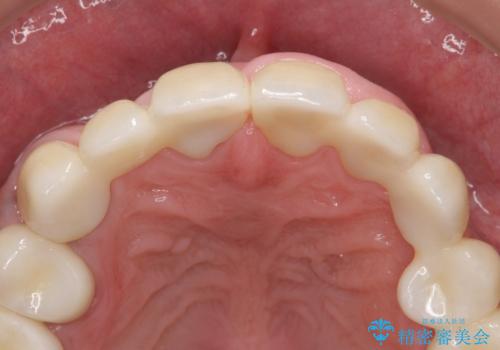

オールセラミッククラウン ブリッジによる欠損歯の補綴

インプラントは希望されなかったため、左側は1番から7番のロングスパンブリッジによる補綴を行いました。

今回用いたオールセラミッククラウンは、ジルコニアフレームという白い素材の上にセラミックを盛っているため審美性が非常に高いのが特徴です。

またジルコニアは人工ダイヤモンドの材料にも使われているほど高い強度を持っており、そのためオールセラミッククラウンは審美性だけでなく、奥歯やブリッジの補綴も可能とするクラウンです。